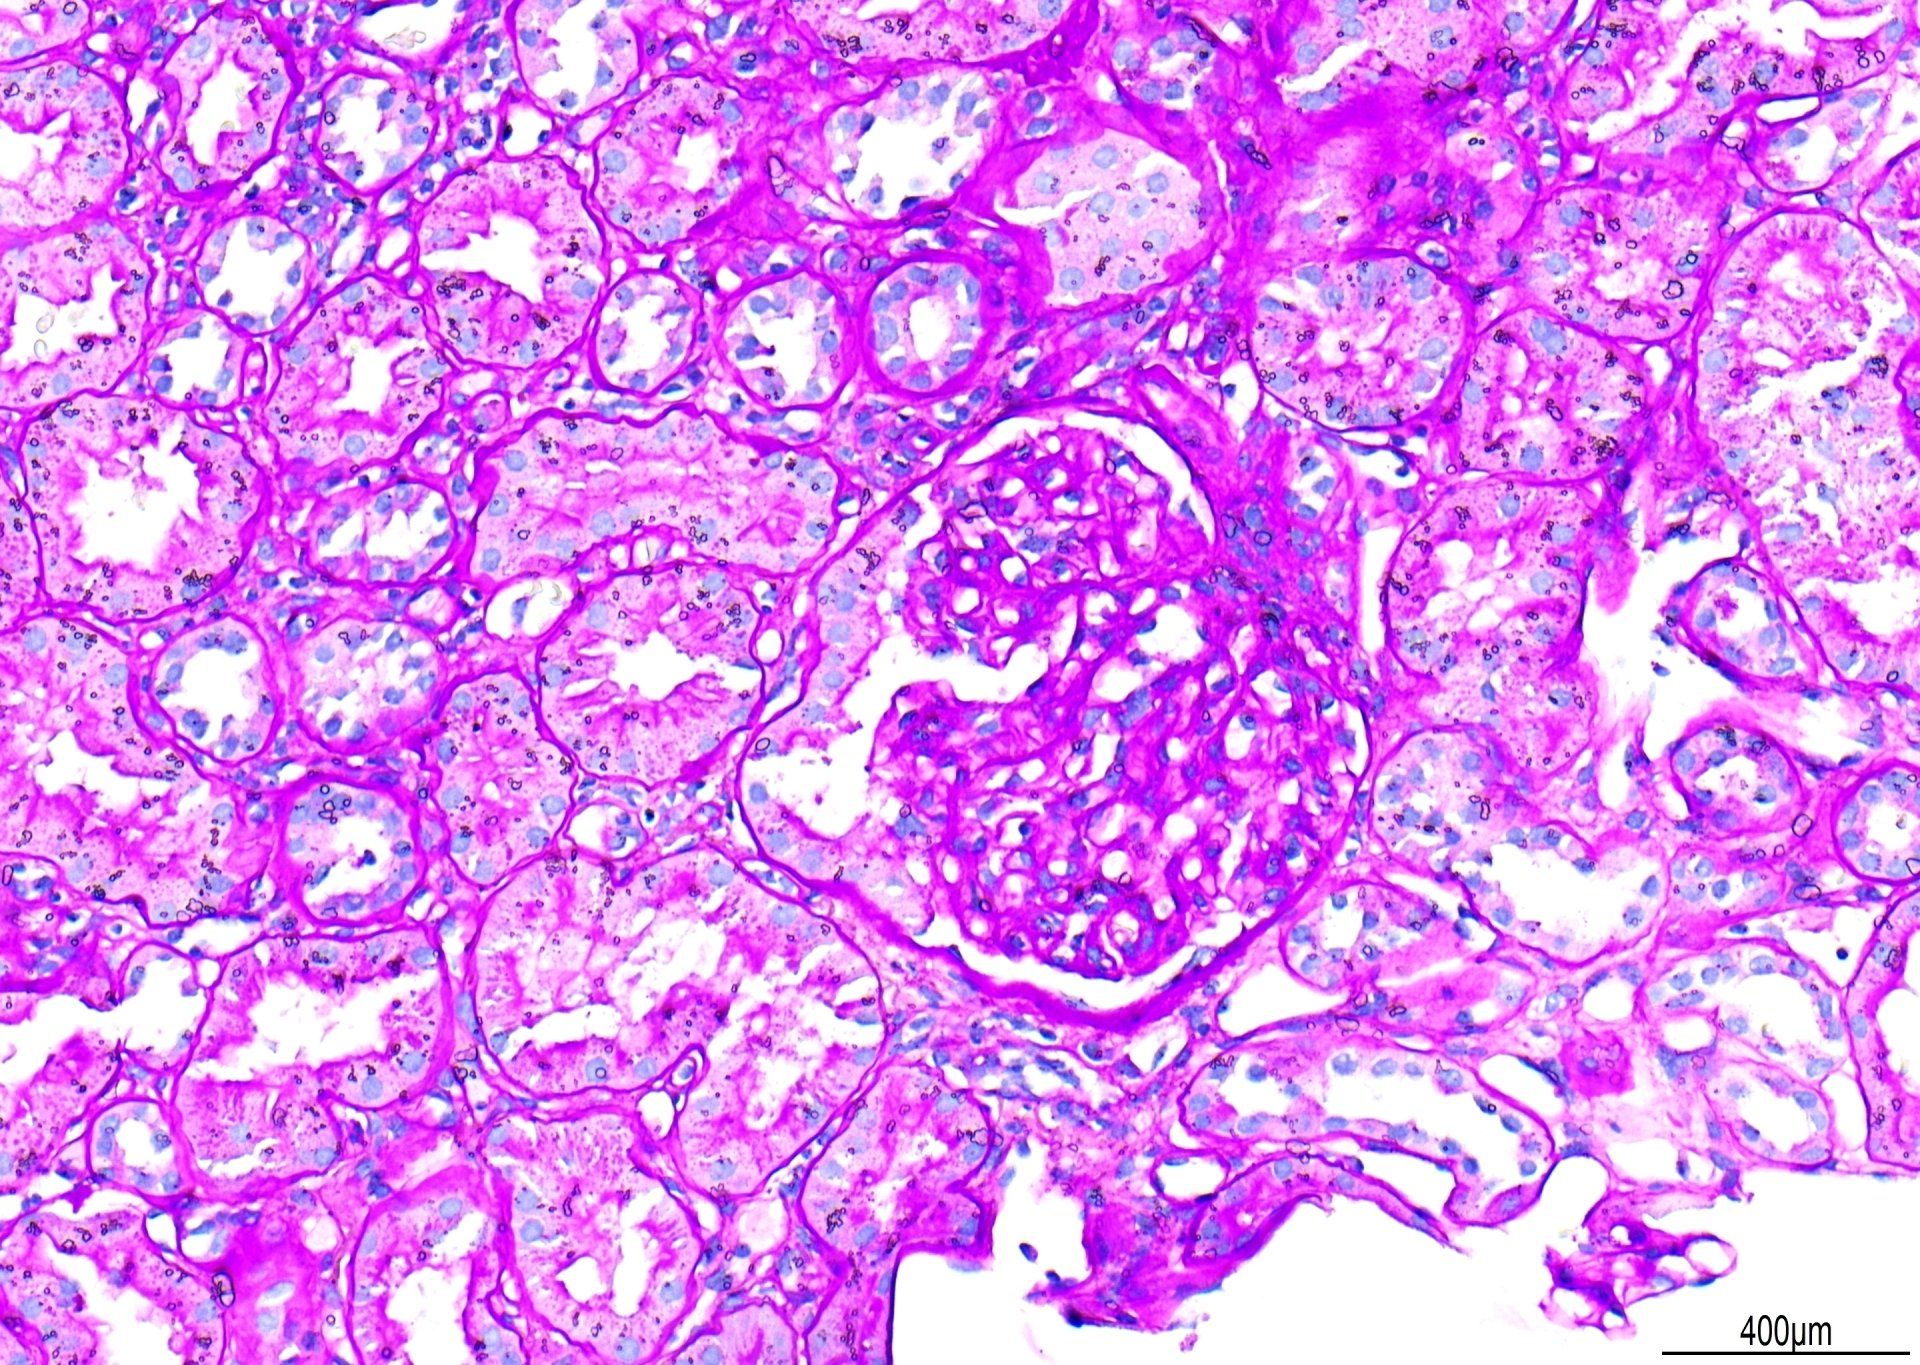

NADH - Spierskema

Hier is 'n voorbeeld van 'n skyfie uit ons Spierskema wat die NADH-metode wys. Hierdie beeld toon 'n uitstekende veseltipe-demonstrasie en het 10/10 by die assessering behaal!